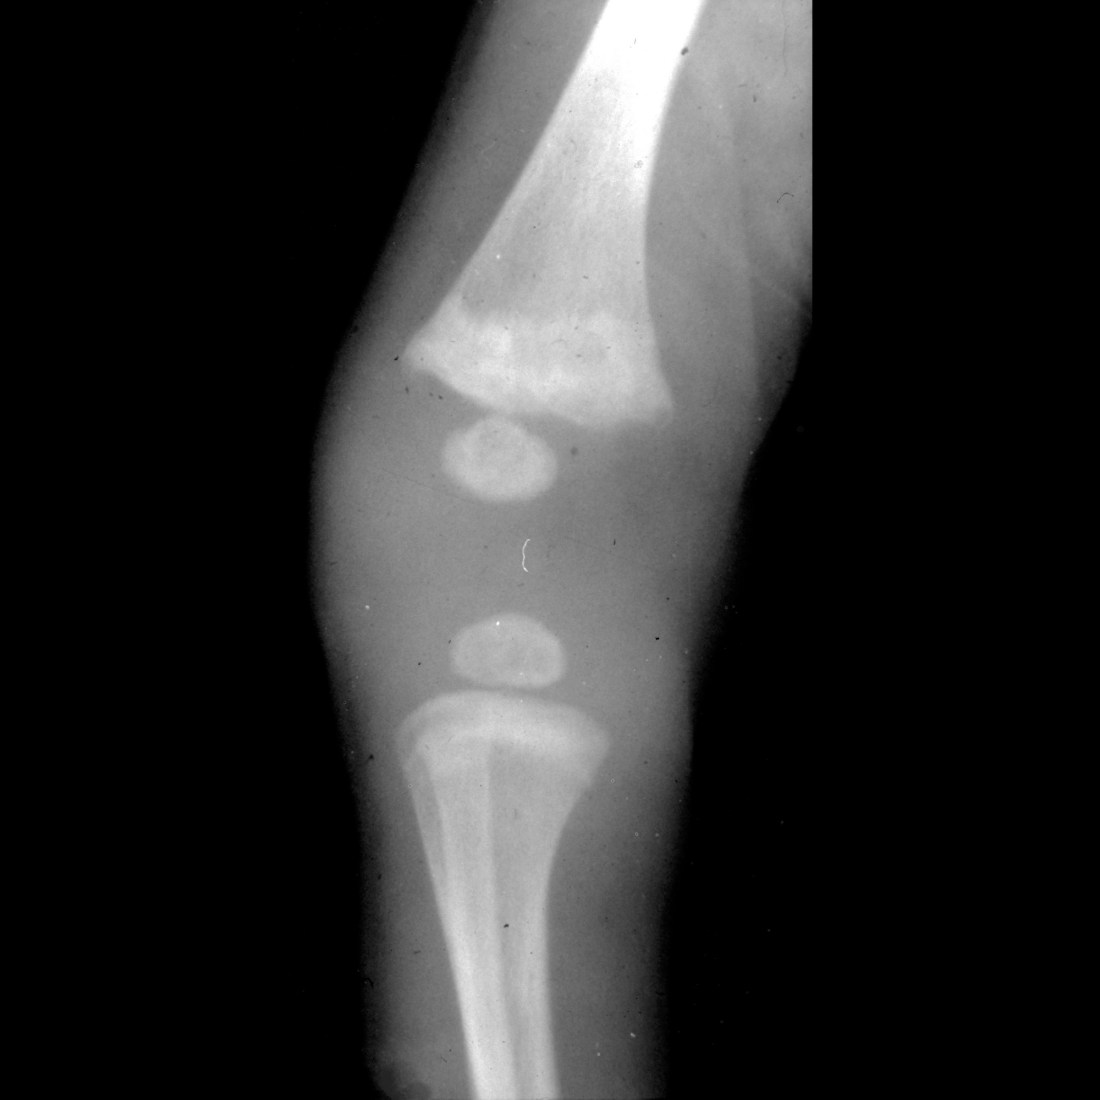

Infant with TORCH infection Pediatric Radiology Case Pediatric Torches Infection Radiology The term torch complex or torches infection refers to the congenital infections of toxoplasmosis, others (syphilis, hepatitis b), rubella, cytomegalovirus (cmv), and. Congenital torch infections are vertically transmitted infections (acquired directly from the mother and transmitted to the embryo,. Infections acquired in utero or during the birth process are a significant cause of fetal and neonatal mortality. In this review,. Torches Infection Radiology.